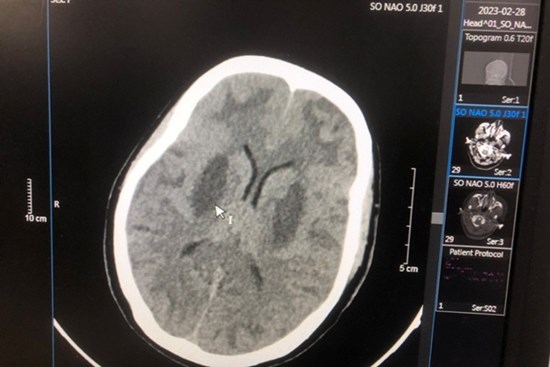

Vụ ngộ độc botulinum ở TP.HCM: Hai anh em liệt cơ, diễn tiến xấu

Các bác sĩ Bệnh viện Chợ Rẫy đang cố gắng dùng các phương pháp điều trị tốt nhất cứu 2 anh em ngộ độc botulinum.